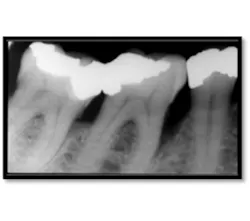

As you can see, the extent of bone loss on the mesial is significant, almost to the apex.14 months post treatment:

MB/ML #12 now probes 3mm (above left), Notice the nice bone fill on the mesial surface (above right)